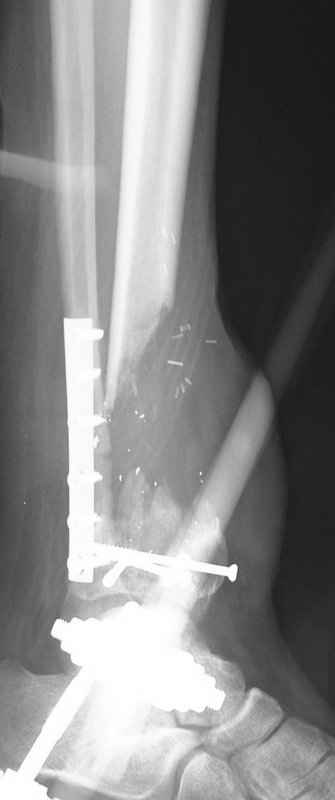

5. Ну и чтобы не быть голословным. Молодой человек подорвался на фугасе (Чечня, 2005 год). Свежие рентгенограммы:

Соответственно ожоги и дефект мягких тканей, переломы костей стопы и пр. Наложили аппарат

Илизарова (как придется), хирургически обработали и героически заживляли мягкие ткани с многочисленными кожными пластиками. В итоге через полгода я принял его вот таким:

Реализовал описанную выше методику, и в итоге вот что получилось. Высылаю лишь прямые проекции,

в боковых тоже всё в тему.

Очень пригодились карбоновые кольца (Джолдас -огромное спасибо, я твой должник!!!), поскольку остеопороз дистального отломка был просто невероятный. На цифровом рентгене с трудом угадывались контуры.

Рентген в процессе перемещения - внизу карбоновые кольца, тракция фрагмента спицами с упором.

внешний вид в аппарате - не завершающем этапе, сначала стопа тоже была фиксирована в аппарате.

Сейчас аппарат сняли, но случай ещё не завершенный.

Признаюсь честно, не совсем уверен в прочности консолидации на стыке косточек. Кроме того, укорочение в районе 6 см. Сейчас реабилитация - ходит опираясь на ногу с одним костылем.

Продолжение, видимо, будет... Возможно, будем удлинять.